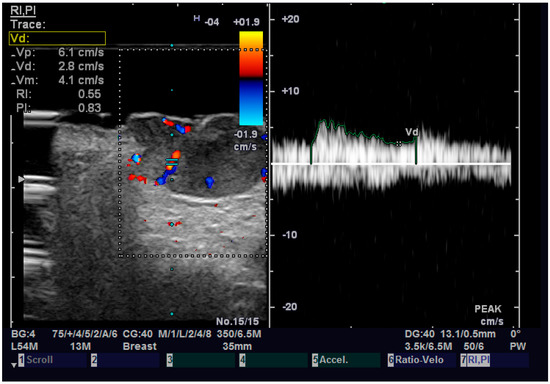

Figure 7.

Doppler examination of a SCC.

Regarding elastography, we can easily see that the tumor tissue is stiffer than the normal adjacent one (Figure 6). We did not find any significant statistical association between the value of strain ratio and the histology of the tumor. The values in the BCC group were also lower than in the SCC group (95% CI −2.98–0.35, p = 0.126). Doppler examination (Figure 7) showed increased values for both systolic and diastolic speed in the SCC group, but the results were not statistically significant and no association between the type of histology and vascularization was found (Table 4).

Table 4.

Pulsatility index, resistive index, strain ratio, diastolic speed and systolic speed related to histopathological type.